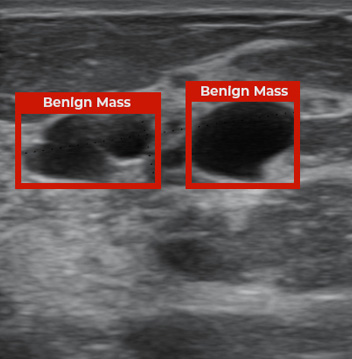

RADIFY® for Ultrasound

RADIFY® AI solution integrated with the mobile ultrasound tool will achieve radiology-level performance for point-of-care diagnosis on ultrasound images. Ultrasound is a relatively inexpensive and portable modality of diagnosis for life-threatening diseases and for use as point-of-care. The procedure is a non-invasive tool and it quickly gives doctors information necessary to make a diagnosis.